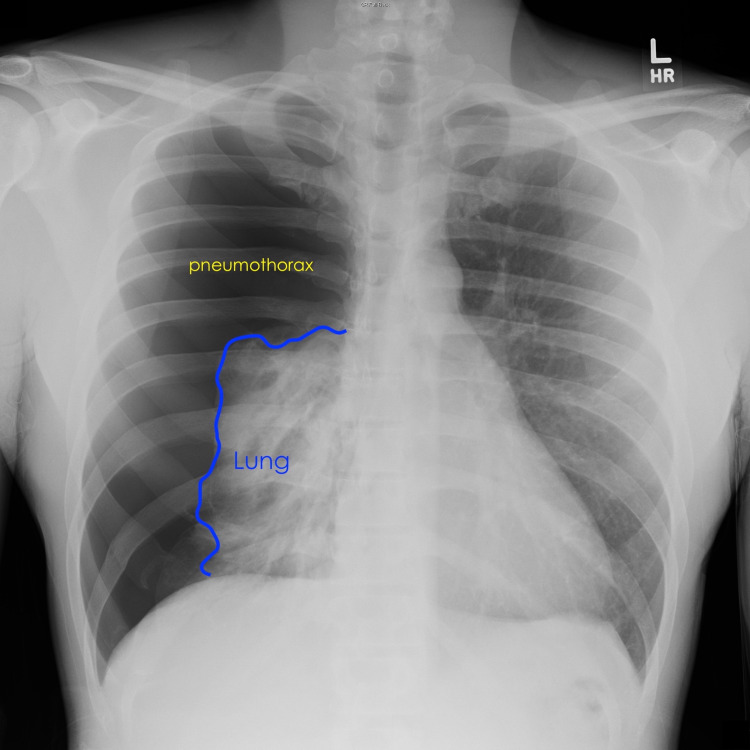

Physical examination of the apprehensive patient revealed absent right lung sounds and shallow breathing. Laboratory analysis was unremarkable. Chest radiograph showed a near-complete lung collapse [Figure 1].